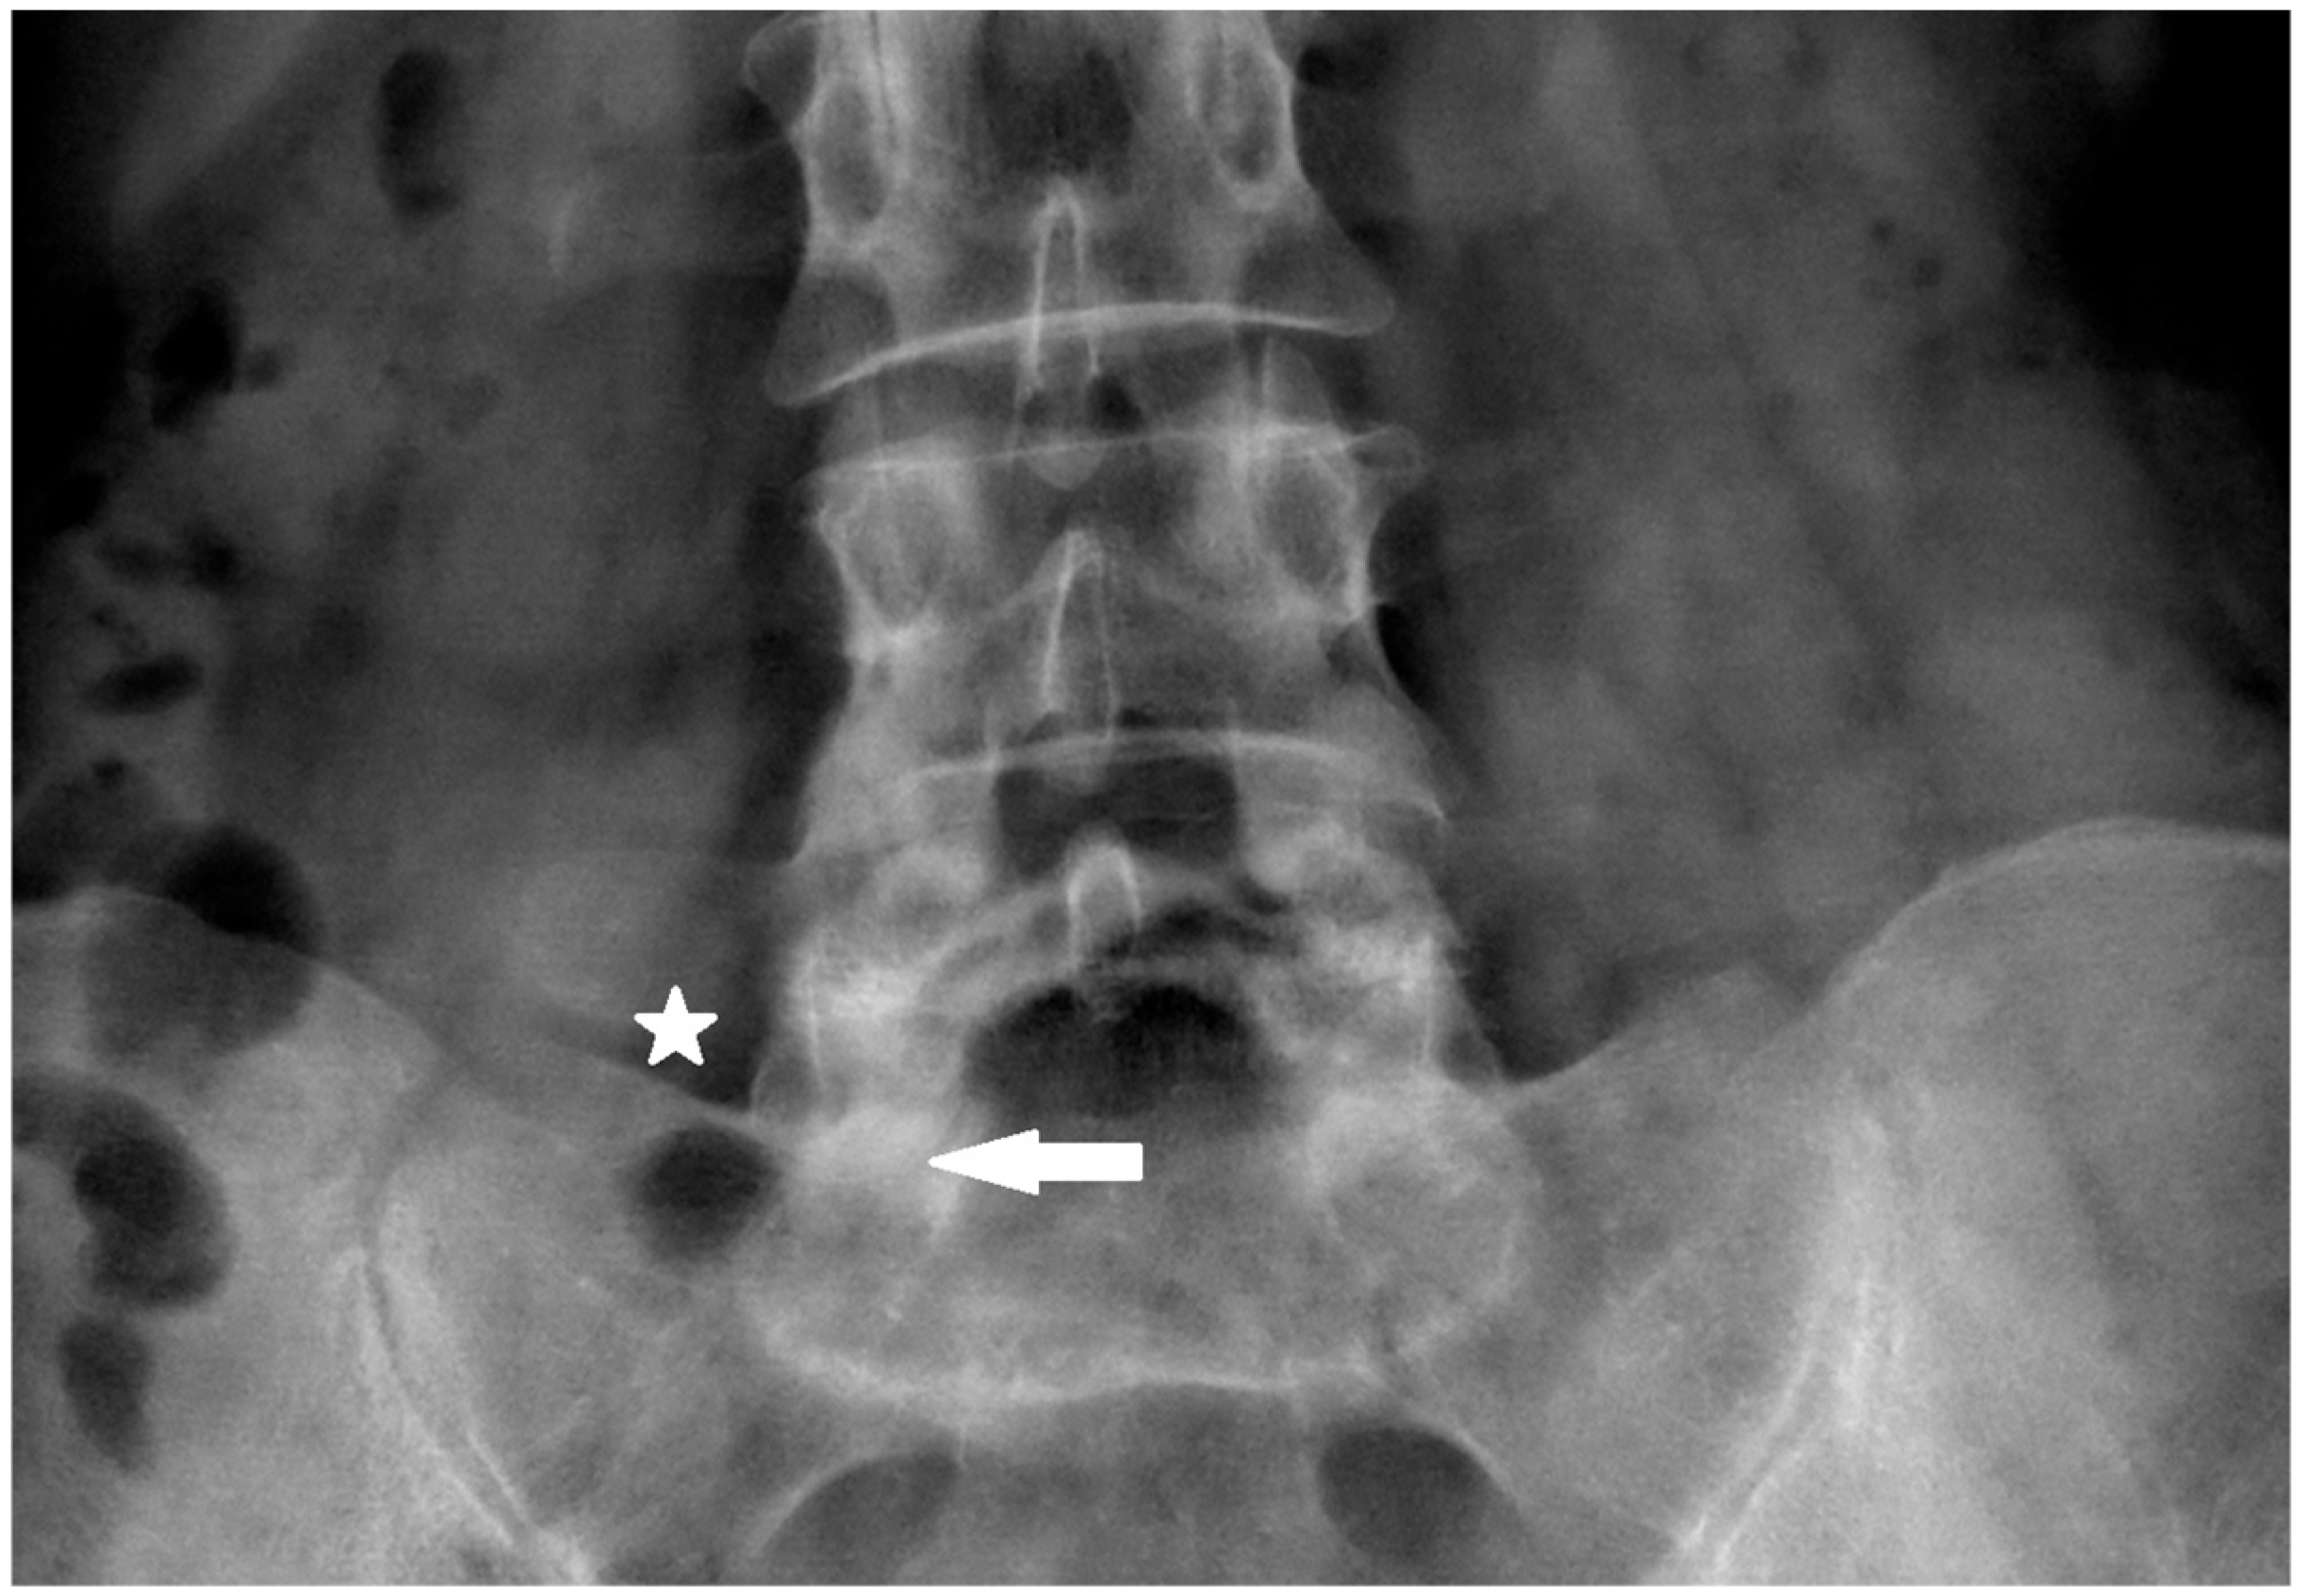

Therefore, the skin entry point is localized at the tip of the L5 transverse process on the same side (Figure 1). This yields the proper inclination of the needle in both planes, the coronal and sagittal.

Figure 1. Skin entry point superior edge or slightly above sacral ala ⅓ lateral part of distance between lateral margin of L5/S1 facet and superior brink of sacroiliac joint (asterisk—skin entry point, arrow—target point of first bone contact).